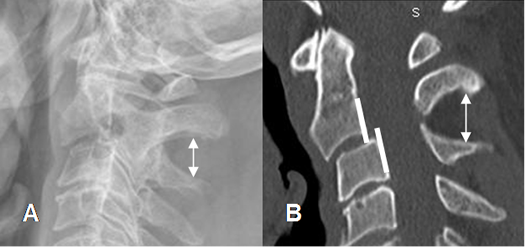

Fig 167. Aumento del espacio interespinoso.

A: Rx lateral y B: TAC reconstrucción sagital. Aumento del espacio entre las apófisis espinosas de C2 y C3, por anterolistesis post-trauma.